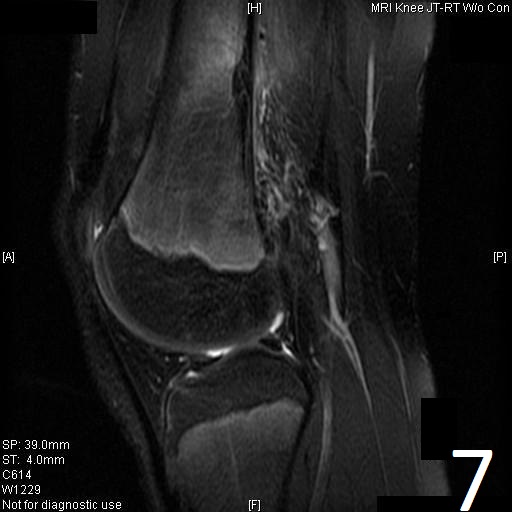

MRI

• Variable heterogeneneous signal on T2 (Fig. 9).

Fig. 6

Fig. 7

Fig. 6-9: Sagittal T1 (Fig. 6) and T2 (Fig. 7) MRI of the knee demonstrates a fibrous cortical defect. Axial T1W (Fig. 8) and T2W (Fig. 9) show a heterogeneous lesion on distal femur, compatible with nonossifying fibroma.